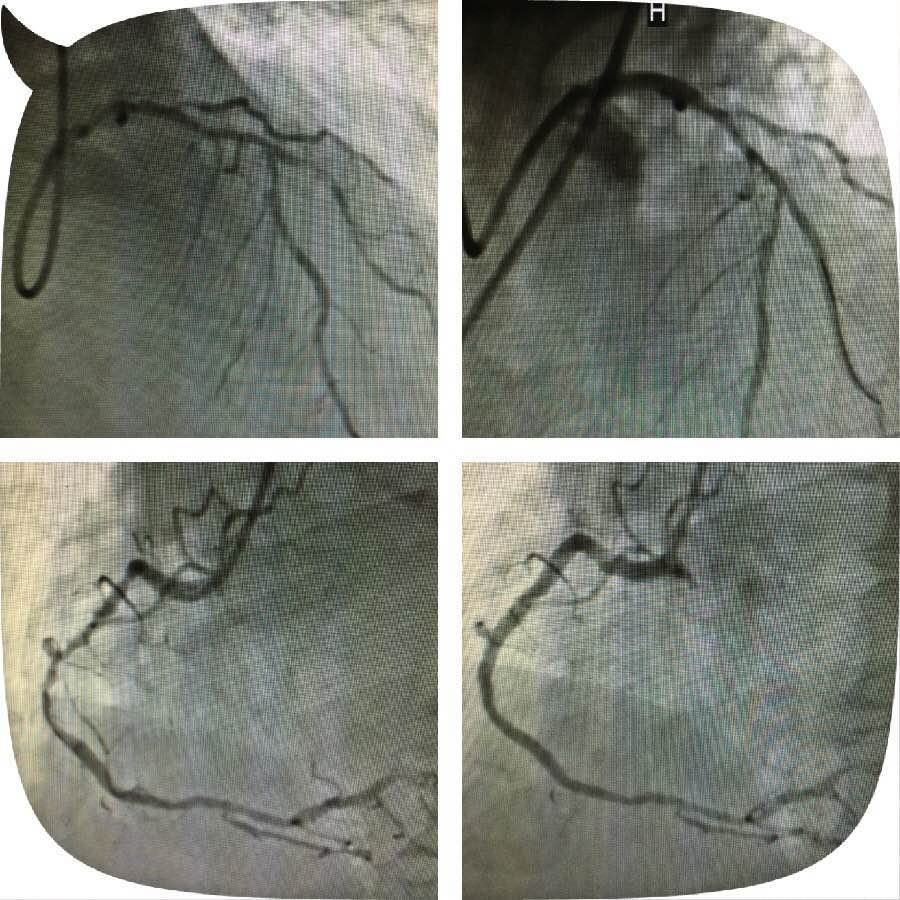

原来,这位老人突发心脏病被送到21点游戏攻略站 心五病区,入院后心电图示非ST段抬高心肌梗死,急诊行冠状动脉造影检查发现左主干钙化严重狭窄,合并右冠脉钙化严重狭窄病变,死亡风险极高。考虑患者病变复杂,贸然行左主干介入治疗风险极高,针对此患者特殊情况,心血管病医院组织专家进行缜密讨论,并与患者及家属充分沟通交流后,制定了血运重建的合理治疗方案。首先完成患者右冠脉钙化并严重狭窄病变的介入治疗,再次应用切割球囊行左主干严重钙化狭窄病变和对角支严重狭窄病变的介入治疗。

实施右冠严重狭窄长病变的介入治疗一周后,患者病情稍有缓解,经心血管病医院专家的缜密讨论,拟行切割球囊治疗患者的左主干钙化并严重狭窄病变,手术由心五病区郭瑄主任及陆艳副主任医师实施。术中如预期情况一样,经普通球囊反复扩张后,左主干的狭窄仍显得“纹丝不动”,患者出现胸痛症状,手术时间延长一分,患者手术风险增加十分,这时应用切割球囊就是关键的利器。手术成功!术中患者各项生命体征平稳,安返病房。